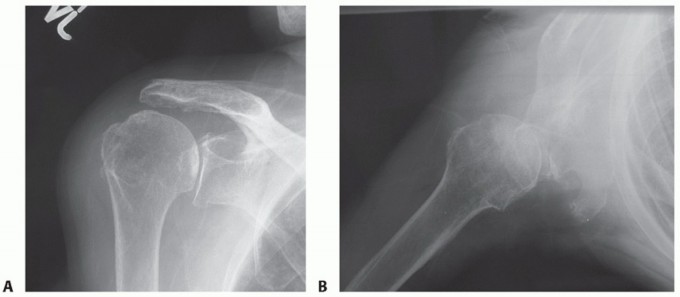

FIG 3 • Radiographic findings consistent with a good candidate for isolated superior latissimus dorsi transfer for irreparable rotator cuff tear. A. True AP radiographic view of the glenohumeral joint showing minimal superior migration of the humeral head and preservation of the joint space. B. Axillary lateral view of the glenohumeral joint demonstrating joint space preservation and the absence of osteophytes with a centered humeral head.*

A true anteroposterior (AP) radiographic view of the shoulder in the plane of the scapula and axillary view is obtained (FIG 3A,B).

This allows evaluation of glenohumeral arthritis, superior migration of the humeral head, and identification of any abnormal bony anatomy (FIG 4A,B).